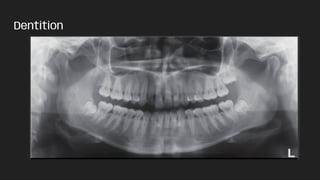

● Dentition

Dentition